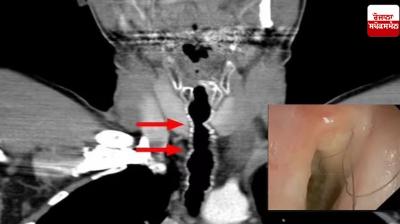

Health News: ਹਰ ਰੋਜ਼ ਪੀਂਦਾ ਸੀ ਸਿਗਰੇਟ, ਹੋਇਆ ਬੁਰਾ ਹਾਲ, ਗਲੇ ਵਿਚ ਉੱਗਣ ਲੱਗੇ ਕਾਲੇ ਵਾਲ